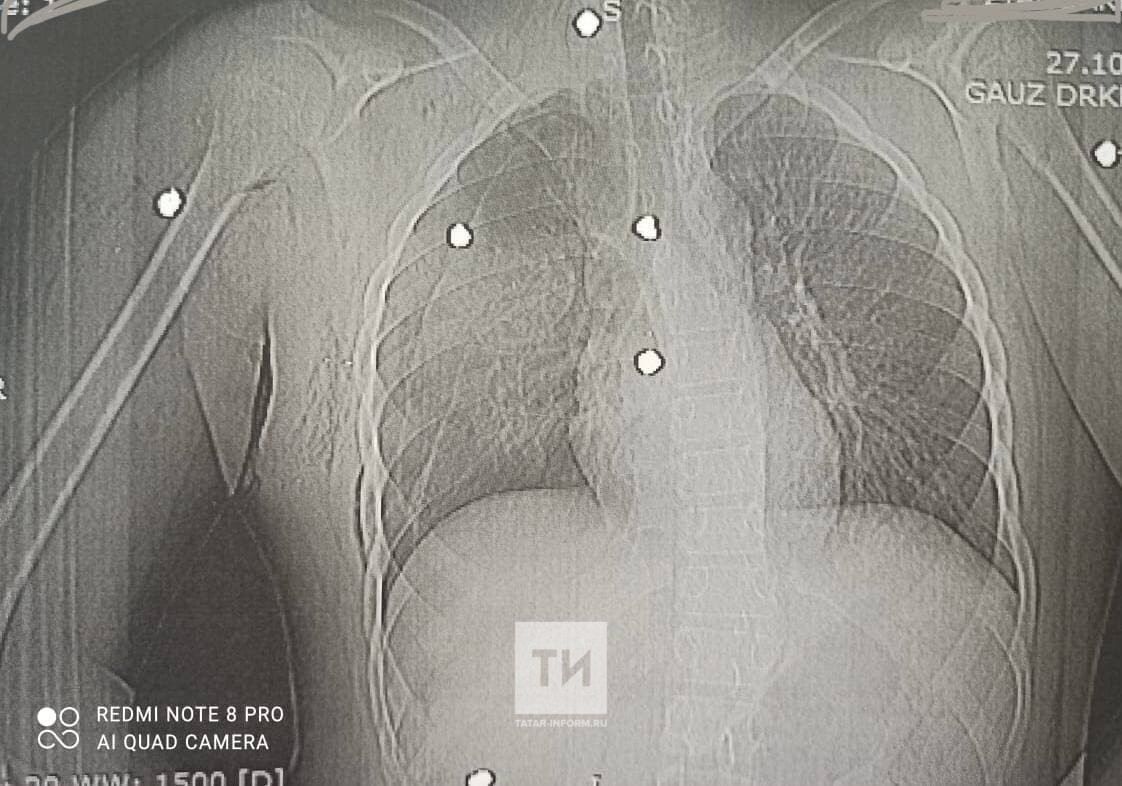

«Конкретно наша бригада торакальных хирургов из РКБ. Мы участвовали в операции с детскими хирургами мальчику 14-летнему с множественными ранениями – это картечь была, ранение грудной клетки с множественными повреждениями правого легкого», – рассказал заведующий торакальным отделением №2 РКБ Евгений Тришин.